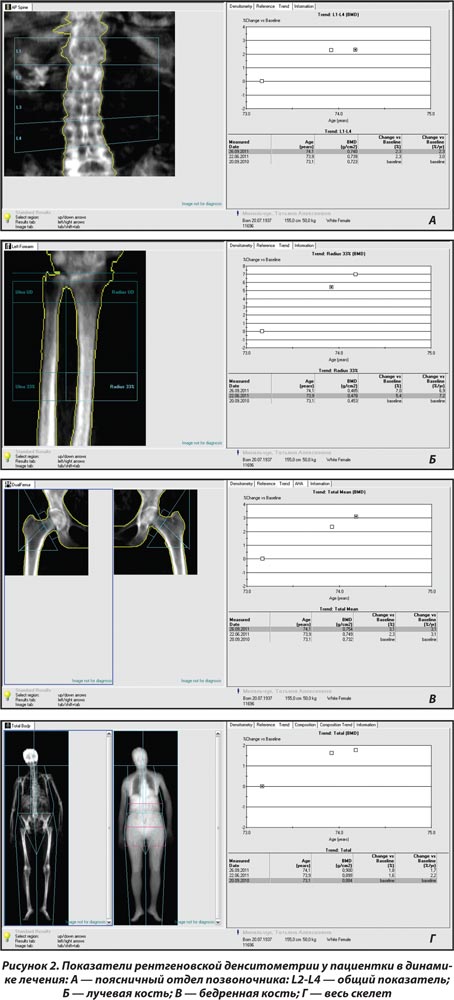

Через 3 мес. наблюдения в связи с системным остеопорозом пациентке назначена антиостеопоротическая терапия препаратом бивалос (по 1 саше 1 раз в день) на фоне приема препаратов кальция и активных метаболитов витамина D. Контроль денситометрических показателей костной ткани через 3 мес. лечения выявил положительную тенденцию МПКТ (рис. 2) на фоне улучшения общего состояния больной.